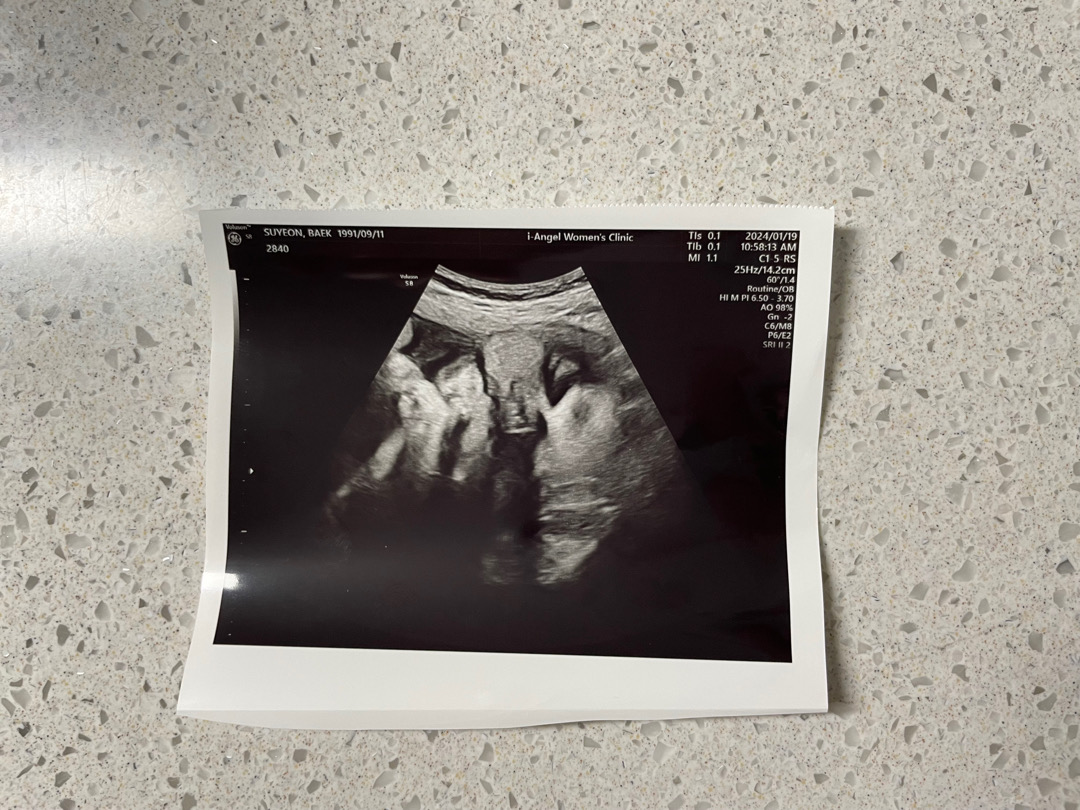

37주 탯줄2바퀴 🥲

오늘 정기 검진 다녀왔어요 37주 1일인데 아직 아기가 완전히 내려오지 않고 둥 떠있다고 하시며 운동하라고 하셨어요 그런데 계속 감고 있던 탯줄 1바퀴가 오늘은 2바퀴 감고 있다며 ㅠㅠ 그러면서 너무 잘 놀고 있다고 하시네요 다음주 내진해보고 자분할지 재왕할지 결정하자고 하시는데 저 운동열심히 해야겠지요?? 그와중에!! 뽈따구가 통실해서 눈이랑 짜부되었다는데 너무 귀여워요🥰 또치맘 예약이네요 ㅎㅎ